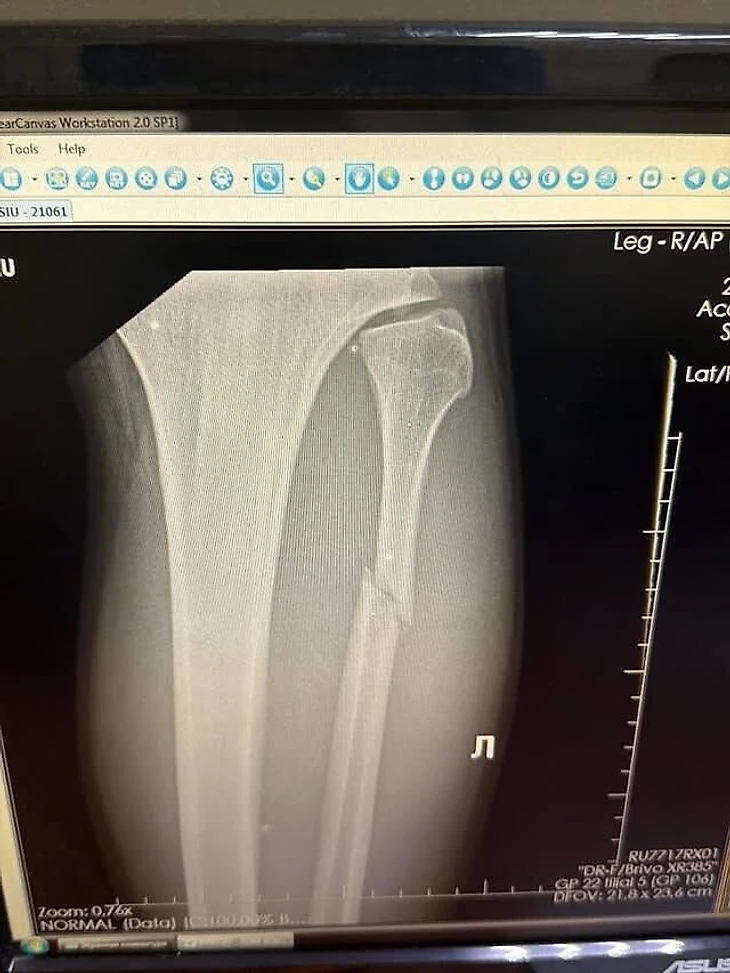

Вальтер Уокер сообщил о переломе ноги.

Вальтер Уокер сломал ногу в бою с Луи Сазерлендом на турнире UFC 321.